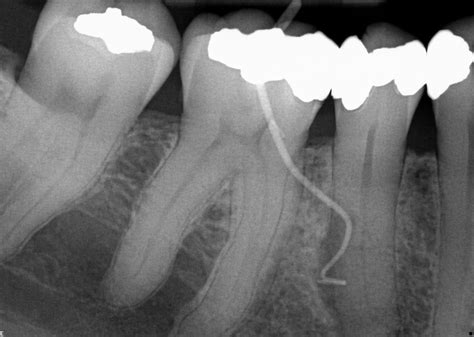

By specializing in the interior health of the tooth, these professionals utilize advanced technology, such as surgical microscopes and digital imaging, to perform intricate procedures. This high level of precision allows them to navigate the tiny, complex canals within the tooth roots to remove bacteria and restore function.

• Root Canal Therapy: The standard procedure for removing infected pulp, cleaning the canal system, and sealing the tooth to prevent future infection.

• Endodontic Retreatment: Sometimes, a previously treated tooth fails to heal or develops new problems months or years later. Retreatment involves reopening the tooth to address the complication.

The actual root canal or surgery involves isolating the tooth, cleaning the canals, and filling them with a biocompatible material called gutta-percha. After the procedure, the tooth is usually capped with a crown or filling to restore it to its full functionality. Most patients find that they can return to their normal daily activities almost immediately.

The field has evolved significantly over the past two decades. Today’s practitioners use ultrasonic instruments that can gently clean the inside of a tooth without the vibration associated with older dental tools. Furthermore, the use of operating microscopes allows the specialist to see tiny, hidden canals that might be missed by the naked eye. These technological leaps ensure that the treatment is not only faster but significantly more effective at preventing the recurrence of infection. By focusing on the microscopic details of the tooth's anatomy, endodontists are successfully saving millions of teeth annually that would have otherwise been extracted.